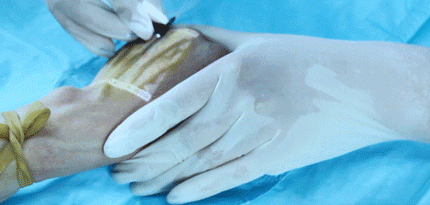

投影式红外血管成像仪

“一针见血”神器

不知大家在医院有没有遇到过

挂水时由于护士找不到血管

被白白扎好几针的经历

那过程想想都瑟瑟发抖

在疫情期间,我国的医疗团队

为提高静脉穿刺效率

便采用了西安中科微光影像技术有限公司

自主研发的投影式血管成像仪

当你把这款仪器照着

需要寻找血管的皮肤区域

它便能直接显示出血管的分布图像

这样医护人员就能

快速地找到血管进行静脉穿刺

以后再也不用白白挨针了

同时它还适用于婴幼儿、老人、

肾病及血管外科等各种临床使用场景

更高级的这仪器的2.0版本

在亮度上还有多种模式可以选择切换

(比如绿光模式、蓝光模式、优化模式

红光模式、紫光模式、深度识别模式等等)

而且还可以拍照

把照片保存在内存卡中

更好的辅助临床进行血管评估

不仅功能强大

外观也很轻巧便捷,可随身携带

该仪器还获得了我国

2019“好设计”金奖